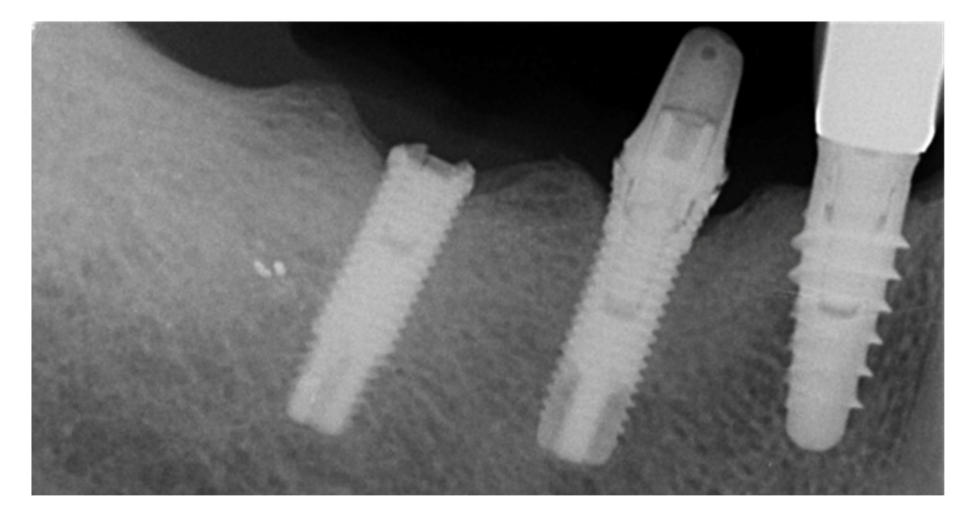

Implants fracture is an untreatable condition. There are several tools that may help clinician to remove the implant. However, fractured implant often presented damaged implant-abutment connection, hence, implant retrieval tools/kits (Figures 1–4) may not work. In cases implant is severely damaged and/or the residual osseointegration is very strong, such us in the mandible, the only possibility is to use a trephine burs (Figures 5–10).